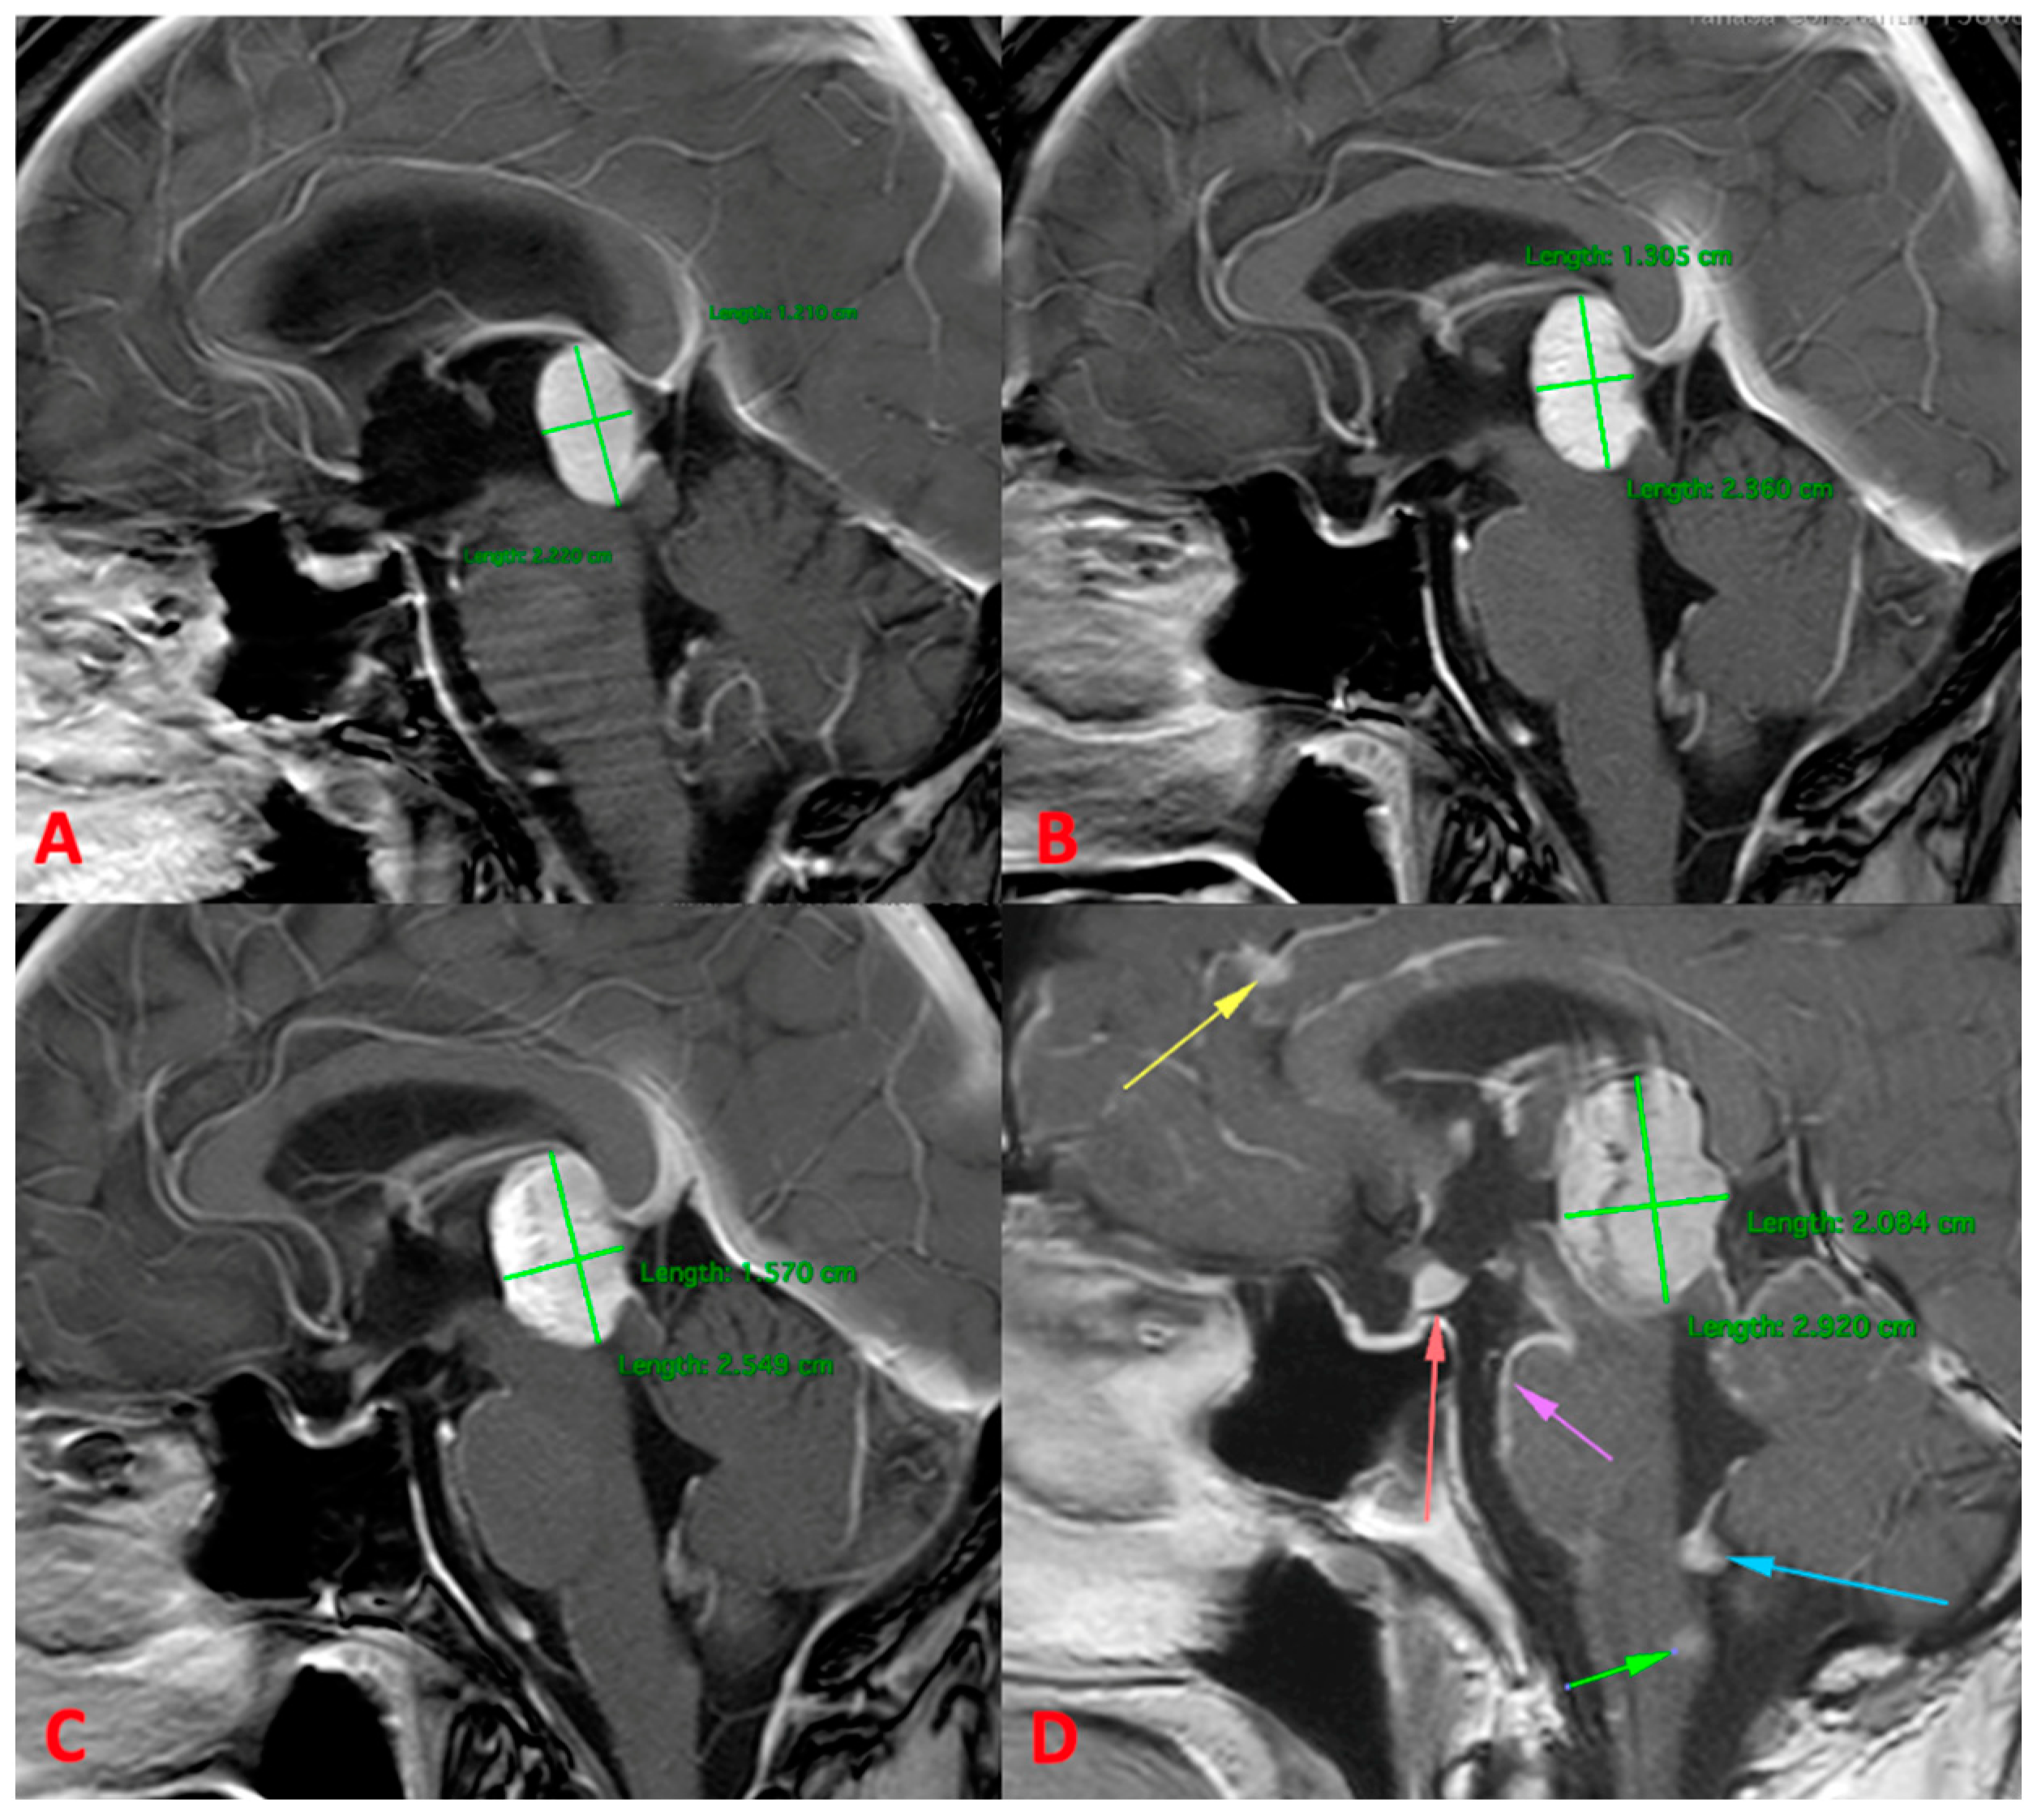

3.2.2. MRI

| Primary pineal melanoma | Extremely rare | Depending on the percent of melanin-containing cell: >10%—hyperintense on T1, hypointense on T2. <10%—hypointense on T1and hyperintense on T2. | |